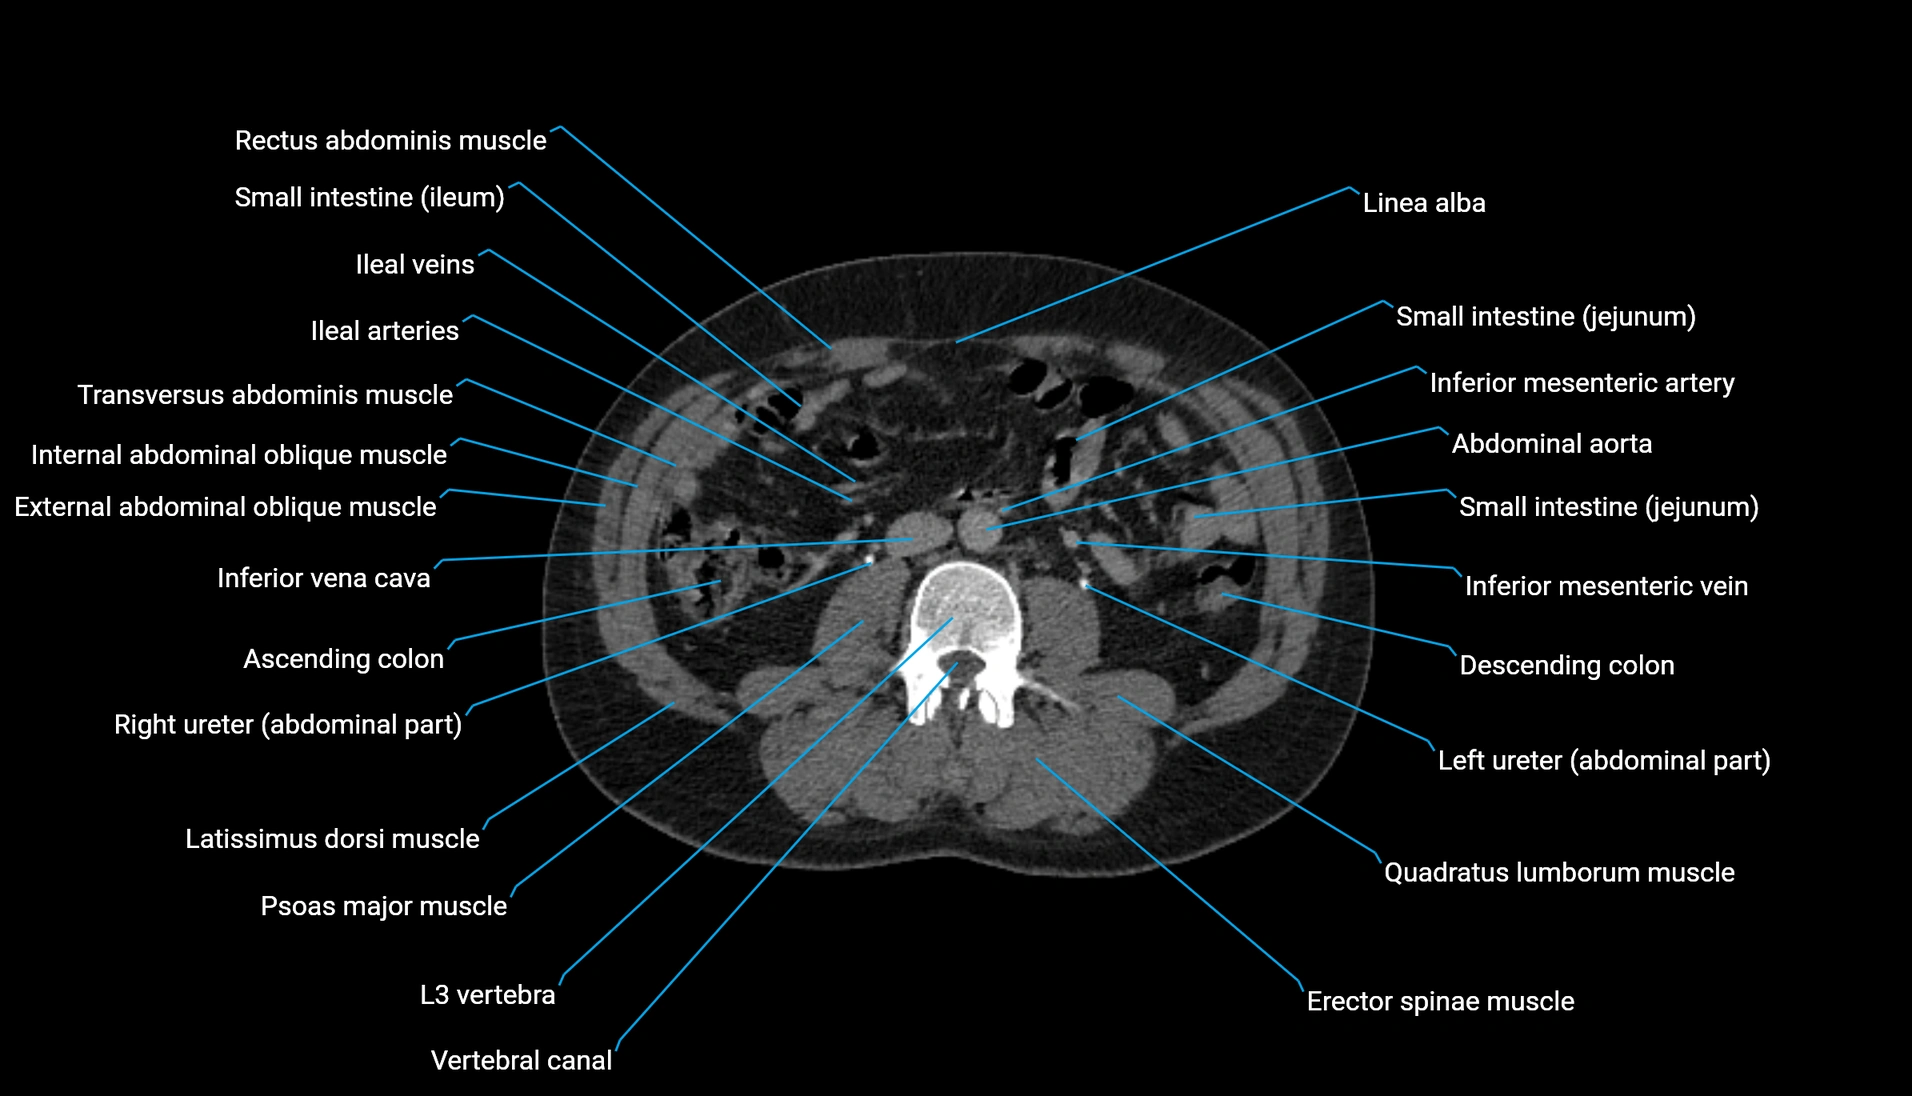

CT Appearance

Non-contrast CT:

-

Demonstrates cortical bone of acetabular rim in excellent detail

Detects fractures, dysplasia, retroversion, or bony overcoverage (pincer impingement)

3D reconstructions used in preoperative hip surgery planning

CT VRT 3D image

CT image